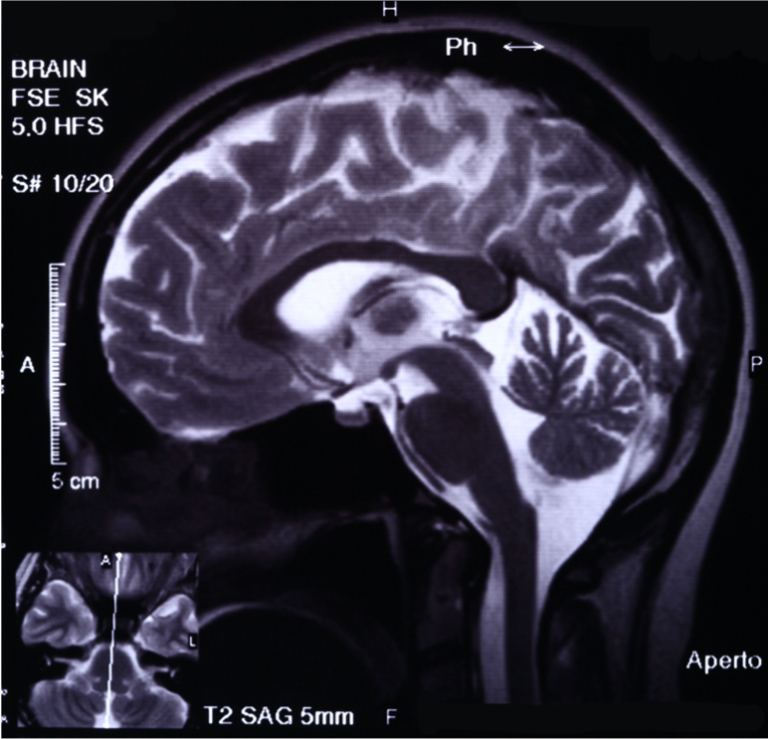

Das Analystenteam von CybelAngel, dem Spezialisten für digitales Risikomanagement, stellt jetzt seinen aktuellen Forschungsbericht „Full Body Exposure“ vor. Demnach sind im Internet weltweit mehr als 45 Millionen medizinische Bilddateien – darunter Röntgen-, CT- und MRT-Scans – auf ungeschützten Servern für jedermann frei zugänglich.

Der Bericht „Full Body Exposure“ basiert auf Untersuchungen von Network Attached Storage (NAS) und Digital Imaging and Communications in Medicine (DICOM), die über sechs Monate hinweg weltweit durchgeführt wurde. DICOM ist der De-facto-Standard, den Mediziner zum Senden und Empfangen medizinischer Daten verwenden. Die Analysten deckten im Rahmen ihrer Recherche auf, dass Millionen sensibler Bilder und Patientendaten im Internet frei zugänglich sind – unverschlüsselt und ohne Passwortschutz.

Für den Bericht scannten die CybelAngel-Tools auf mehr als 2.140 Servern rund 4,3 Milliarden IP-Adressen in 67 Ländern. Dabei wurden mehr als 45 Millionen medizinische Bilder identifiziert, die für jedermann offen zugänglich waren. Allein in Deutschland fanden die Analysten in den letzten sechs Monaten auf 251 Servern 39.204 frei zugängliche DICOM-Aufnahmen. In Großbritannien wurden im gleichen Zeitraum auf 90 Servern 23.238 solcher Bilder entdeckt. Die medizinischen Aufnahmen enthielten bis zu 200 Zeilen Metadaten mit persönlichen Informationen, die eine zweifelsfreie Identifizierung der betroffenen Patienten ermöglichte. Die Daten ließen sich aus allen identifizierten Quellen problemlos ohne Benutzernamen oder Passwort abrufen. In einigen Fällen akzeptierten Login-Portale auch leere Benutzernamen und Passwörter.